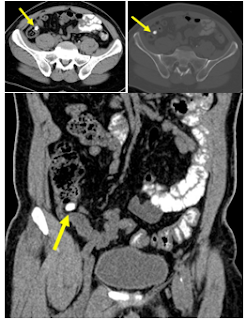

A well-defined echogenic focus measuring 4.0 mm calculus is noted, showing posterior acoustic shadowing.

Pelvicalyceal system is not dilated.

No evidence of hydronephrosis or focal mass lesion is seen.

Hepatomegaly noted.

Bilateral renal calculi (nephrolithiasis) seen with echogenic foci showing posterior acoustic shadowing.

No obvious hydronephrosis / obstructive uropathy detected (if applicable).

The findings demonstrate an enlarged liver consistent with hepatomegaly,

along with the presence of calculi in both kidneys (bilateral renal calculi).

The renal stones may vary in size and location, with possible posterior acoustic shadowing.